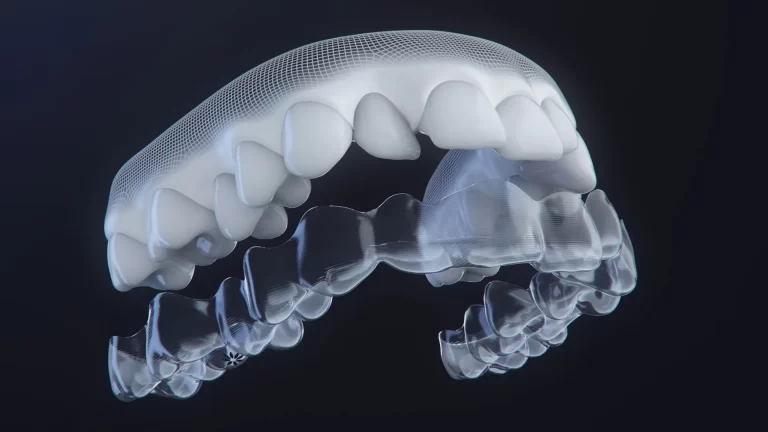

Diş eksiklikleri, hem estetik hem de fonksiyonel açıdan kişilerin yaşam kalitesini doğrudan etkiler. Bu soruna en kalıcı ve doğal çözümlerden biri olan dental implant tedavisi, günümüzde diş hekimliğinde en çok tercih edilen uygulamalardan biridir. Özellikle “Alanya diş klinikleri”, “Kahta implant tedavisi”, “Adıyaman diş implantı” gibi aramalarda sıkça karşımıza çıkan bu yöntem, eksik dişlerin yerini titanyumdan üretilen yapay köklerle doldurarak, doğal dişlere en yakın formda bir çözüm sunar.

- Doğal diş görünümü ve çiğneme fonksiyonu sağlar.

İlk olarak detaylı bir muayene ve çene röntgeni ile planlama yapılır. Uygun görülen çene bölgesine titanyum implant yerleştirilir. Yaklaşık 2-3 aylık iyileşme sürecinden sonra üzerine porselen diş protezi yerleştirilir.